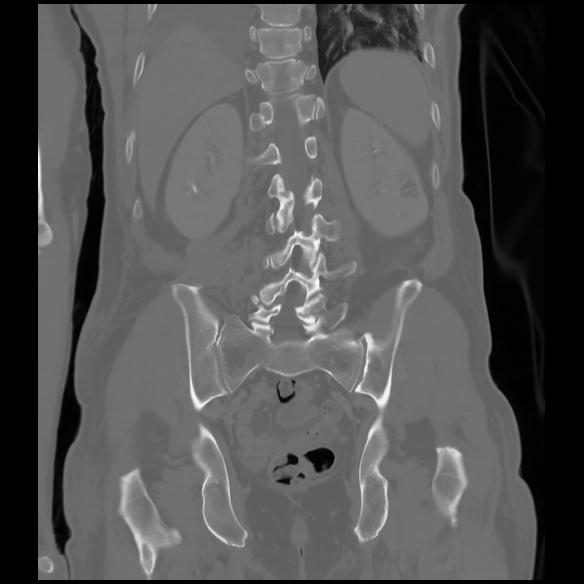

6 CUERPO,CE,Coronal,3.000,CUERPO,Coronal,